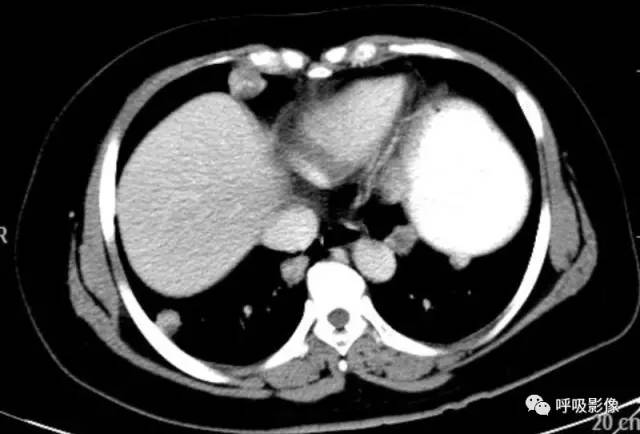

胸部CT示双肺多发结节影,强化明显,内见明显坏死,提示血供丰富。

转移瘤多具有原发肿瘤特点,本例转移瘤为生殖源性肿瘤,盆腔附件包块穿刺活检细胞学检病理均查见恶性肿瘤细胞,结合转移灶坏死、强化明显,需考虑绒毛膜癌可能。

胸部CT双肺多发结节影,强化明显,内见明显坏死,提示血供丰富,这是诊断关键。